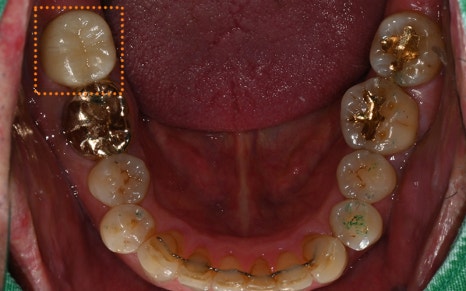

✅ Prosthetic restoration completed after treatment!

The prosthetic work has been completed precisely,

with careful consideration of the occlusion!

In addition, for the lower teeth,

a crown restoration was planned

to correct the occlusion caused by supra-eruption.